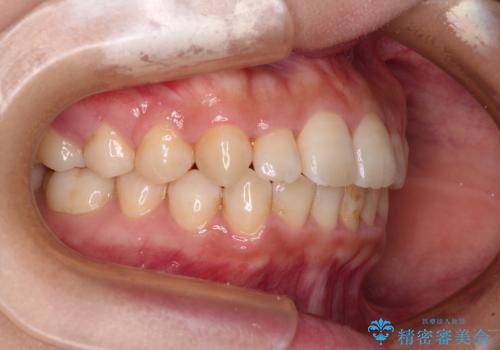

治療前にお伝えした治療期間は1~1年半でして、1年4か月の期間で終えることができました。

ワイヤー矯正は見た目や装置が当たることでの痛みを気にされる方が多いですが、月1回来院して処置をしてもらうだけで歯並びが整うため、大変お勧めです。